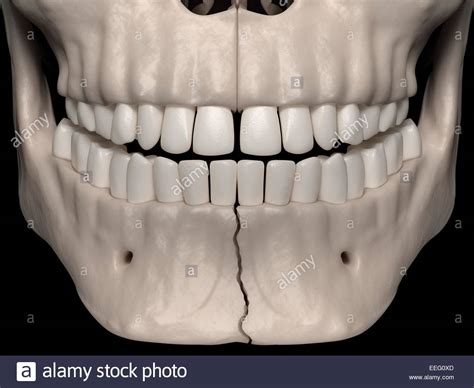

Understanding the Jaw Bone

The jaw, or mandible, is the largest and strongest bone in the face. It plays a crucial role in functions such as chewing, speaking, and facial expressions. The jaw is connected to the skull by the temporomandibular joints (TMJ), which allow for the movement of the jaw. A jaw bone broken can disrupt these functions and cause significant discomfort and pain.

Jaw Bone Anatomy